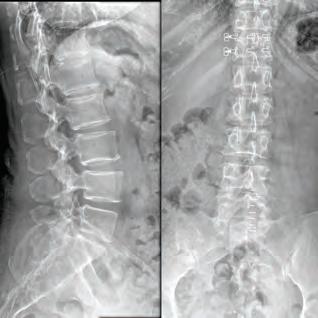

Inspired by the patients he’s cared for there, Dr. Courtney made education a priority. He was salutatorian of his high school class and went on to graduate summa cum laude from Northeast Louisiana University. While at Louisiana State University Medical School, he utilized his summer to perform spine biomechanical tests on human spine cadavers utilizing pedicle screws. Considered cutting edge biomechanics and technology at that time, most spine surgeons didn’t even know they existed yet. However, Dr. Courtney performed one of the first biomechanical tests on those implants. It was a feat that earned him the Howmedica Biomechanic Award and the Louisiana Orthopedic Association Award. He also placed fourth in the World Congress for Student Research Competition.

This realization inspired Dr. Courtney to design, develop, biomechanically test, complete FDA testing and oversee quality control and validation on a host of tools he created. To date, Dr. Courtney has developed nine spinal product lines and obtained nine patents and 14 trademarks on spine related products.

Led by Dr. Courtney, the skilled team at Advanced Spine Center cares for patients with neck and back pain using a wide array of the most state-of-the-art tools and techniques—from conservative physical therapy and injection therapy—to advanced pain manage-

ment, as well as surgical intervention. We employ the latest in minimally invasive spine surgeries, in addition to cutting-edge replacement technology. Incorporating both high tech and high touch, we get our valued patients back to their lives so they can enjoy all the activities they love.

SURGERY: L5/S1 360° LUMBAR FUSION

SURGERY: LEFT L5/S1 MICRODISCECTOMY

SURGERY: C4/C5, C5/C6, C6/C7 ACF (ANTERIOR CERVICAL FUSION)

SURGERY: L4/5, L5/S1 360° LUMBAR FUSION